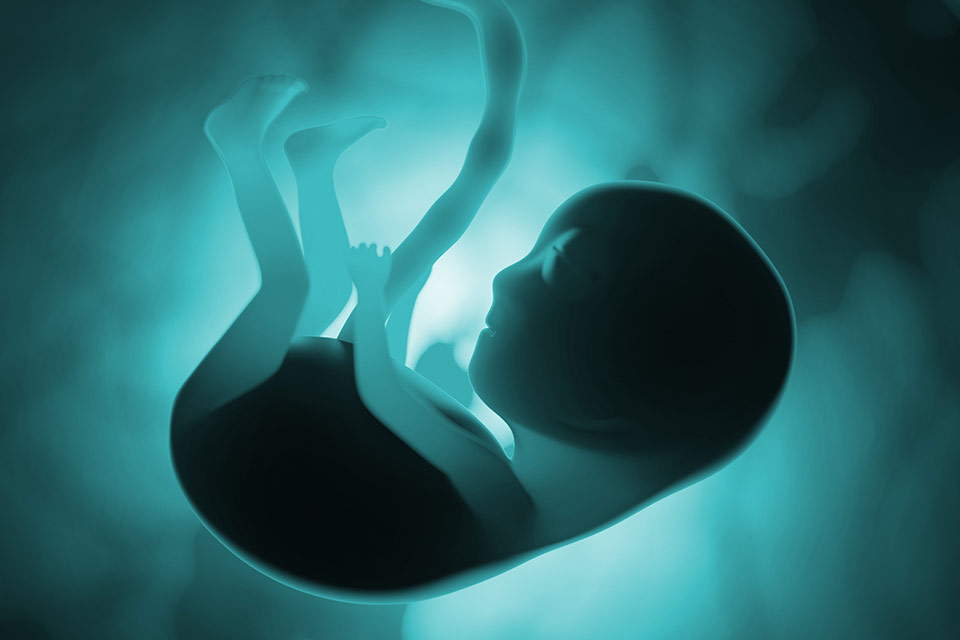

Снимки Леннарта Нильсона: развитие ребенка в утробе

Раздел: Мудрость в фокусе